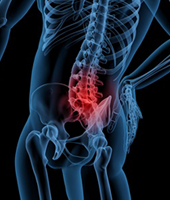

허리디스크

척추 뼈와 척추 뼈 사이에는 존재하는 디스크가 여러 가지 이유로 터져 나와서 신경을 누르며 허리통증을 유발하게 되는 것입니다. 심한 경우 다리가 당기고 저리는 증상이 나타날 수 있으며, 마비증상과 감각이상까지 나타나게 됩니다. 튀어나온 정도와 증상에 따라서 비수술적 치료부터 다양한 수술적 치료방법이 적용되게 됩니다.

디스크의 증상이 초기인 경우에는 물리치료나 약물치료가 주된 치료법입니다. 초기 증상이라 함은 통증이나 저린 증상이 있으나 일상생활에는 견딜만한 정도입니다. 보통 약 4-6주를 이 방법으로 치료합니다. 그러나 통증이 심하여 잠을 자기가 힘들거나 일상생활(외출, 회사일, 집안일)에 지장이 있는 정도거나 증상이 경미하여도 6-8주의 물리치료와 약물치료에 효과가 없다면 수술적 치료를 고려하게 됩니다. 수술 치료는 현미경을 이용하여 간단하게 튀어나온 디스크를 제거하는 방법이 있으며 심한 경우는 디스크를 제거하고 그 공간을 인공 디스크나 뼈로 대체하는 방법이 있습니다.